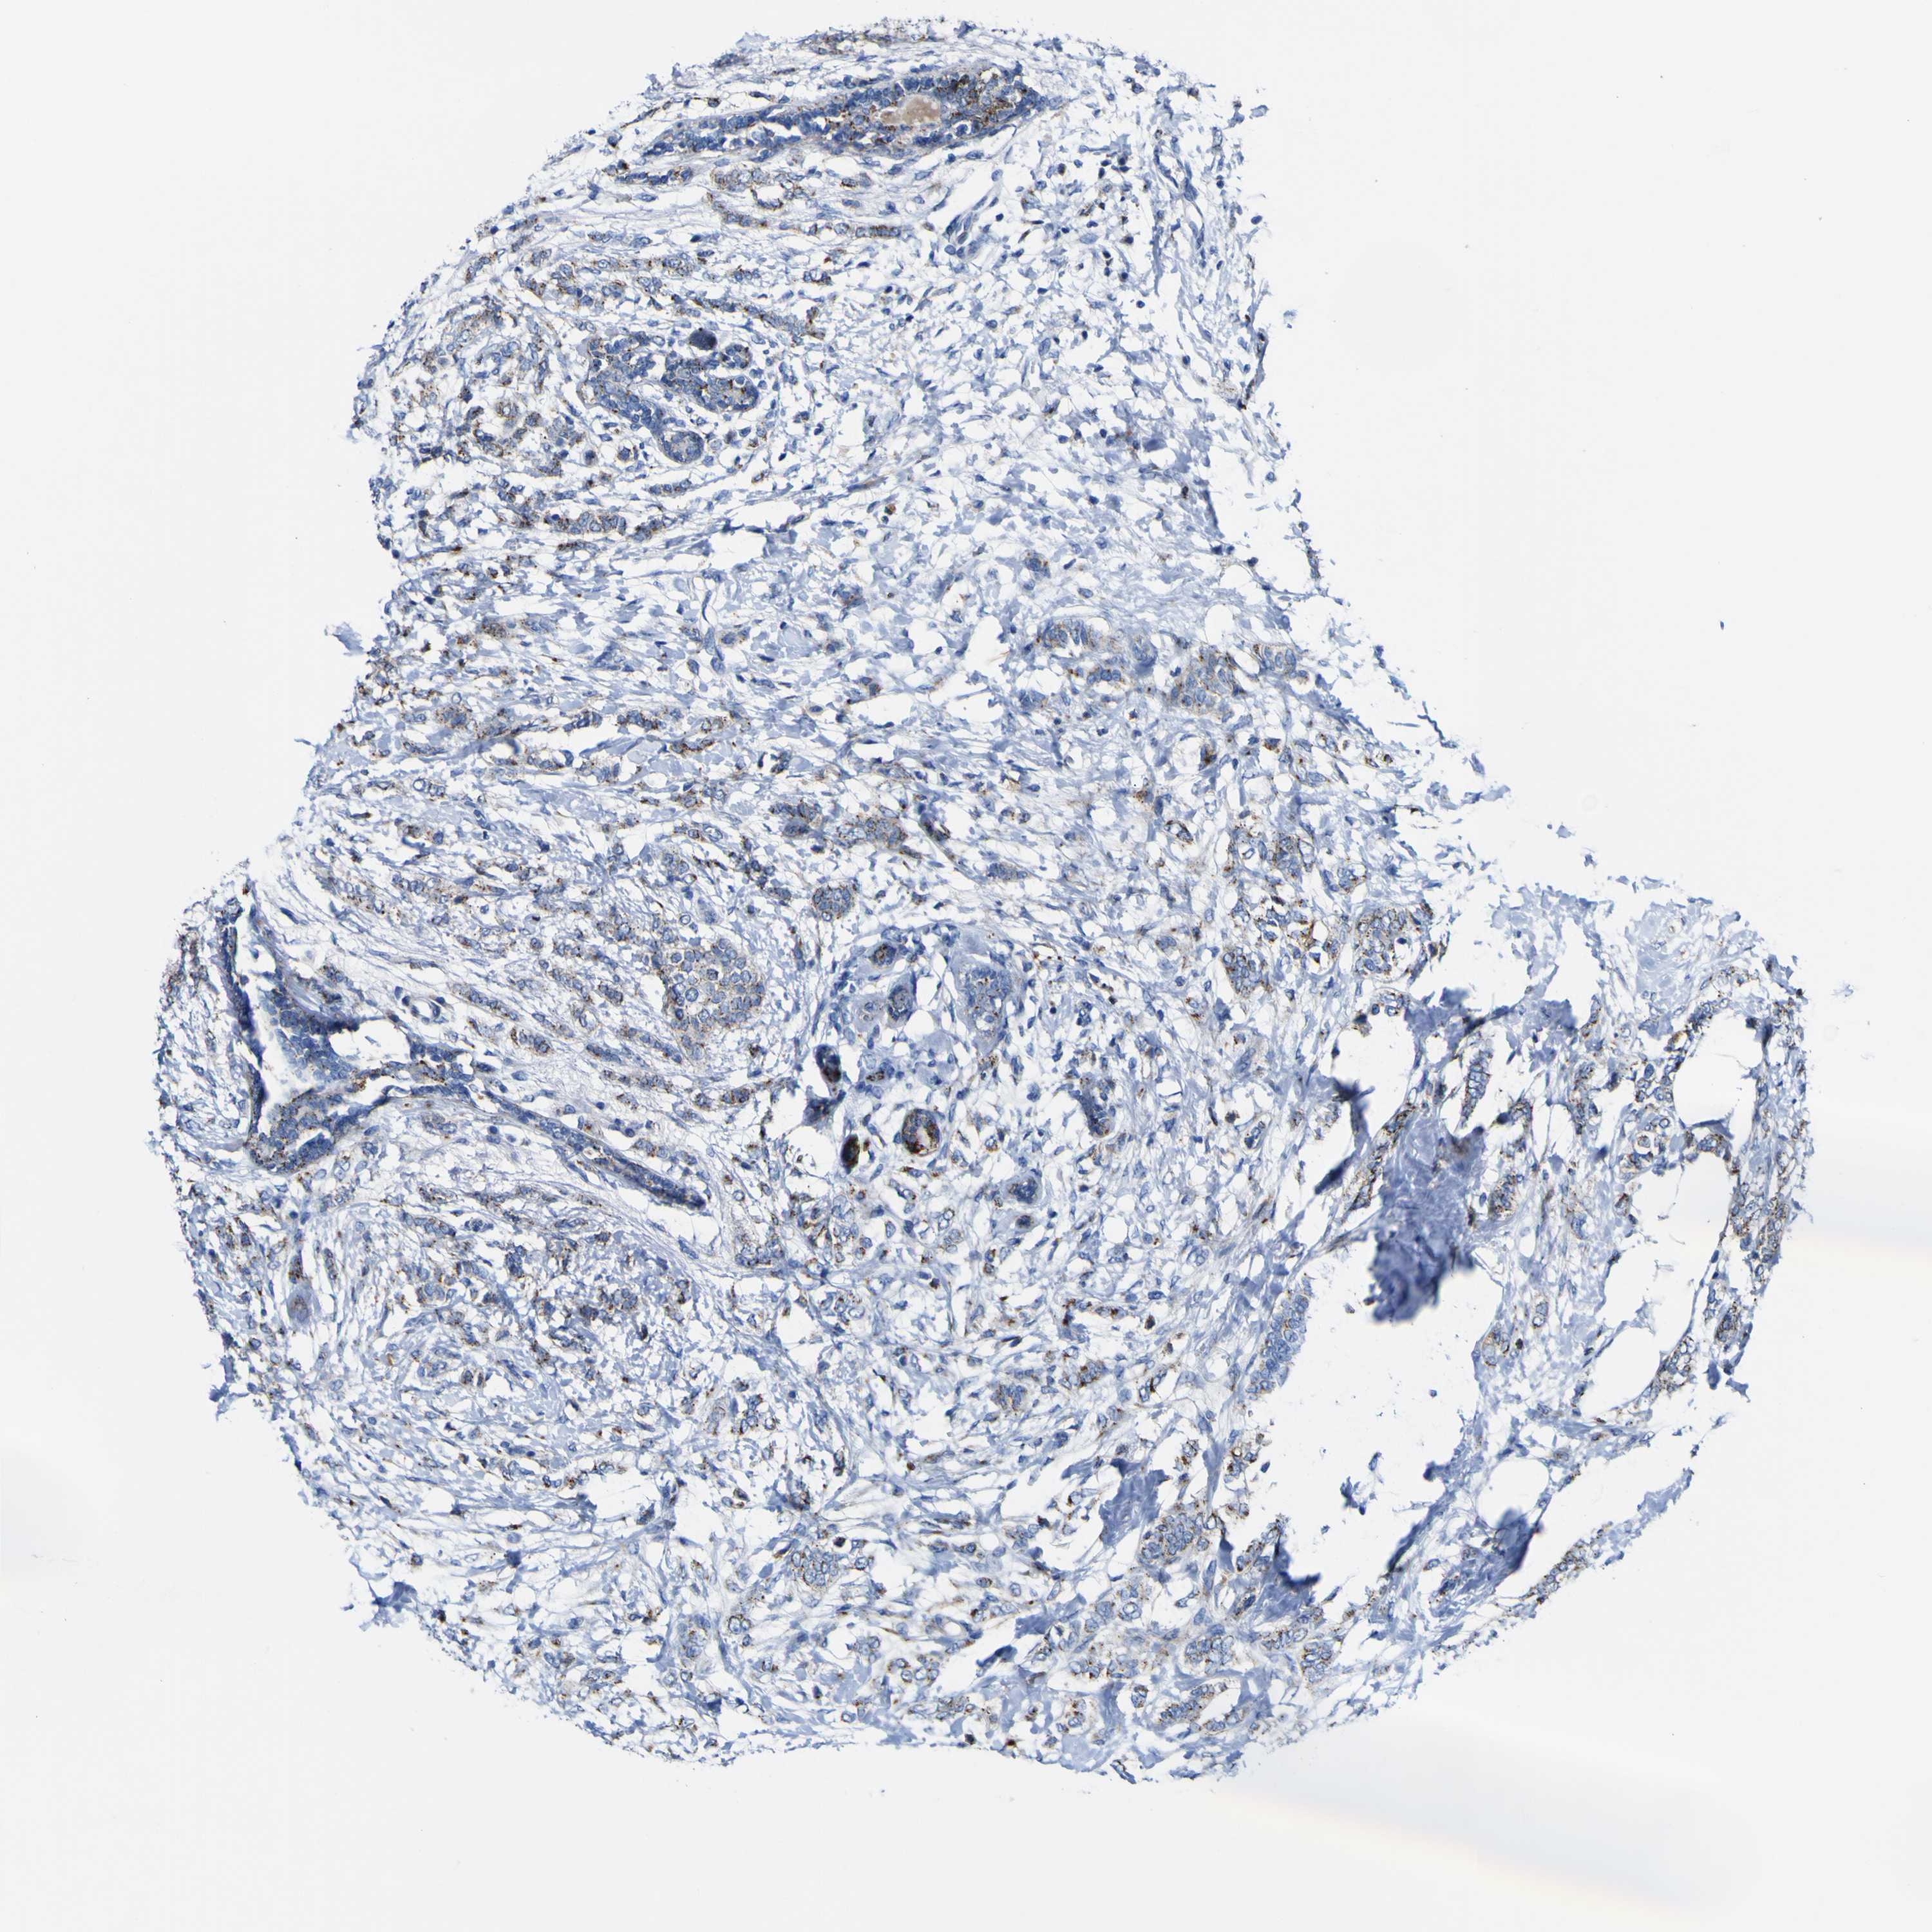

CANCER BREAST CANCER Show tissue menu

BRCA TCGA BRCA VALIDATION PROTEIN EXPRESSION